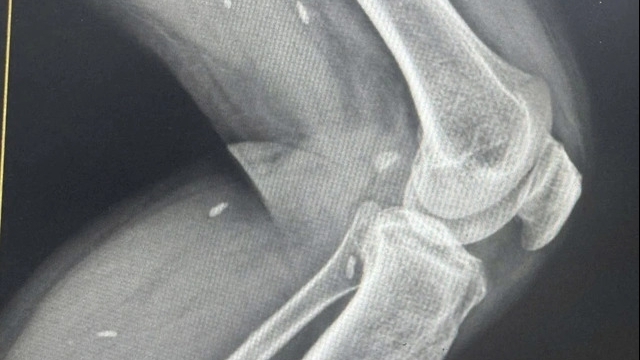

| Hình ảnh chup MRI ghi nhận niêm mạc tử cung dày 13 - 15mm của bệnh nhân N.L.A |

Trước dấu hiệu bất thường trên siêu âm, bệnh nhân được chỉ định chụp MRI (chụp cộng hưởng từ) có tiêm thuốc đối quang từ và ghi nhận hình ảnh cổ tử cung đường kính ngang 34mm. Niêm mạc tử cung dày 13-15mm, phát triển lan tỏa từ buồng tử cung đến ống cổ tử cung. Ranh giới của nội mạc tử cung với cơ tử cung rõ. Nội mạc tử cung ngấm thuốc kém sau tiêm.